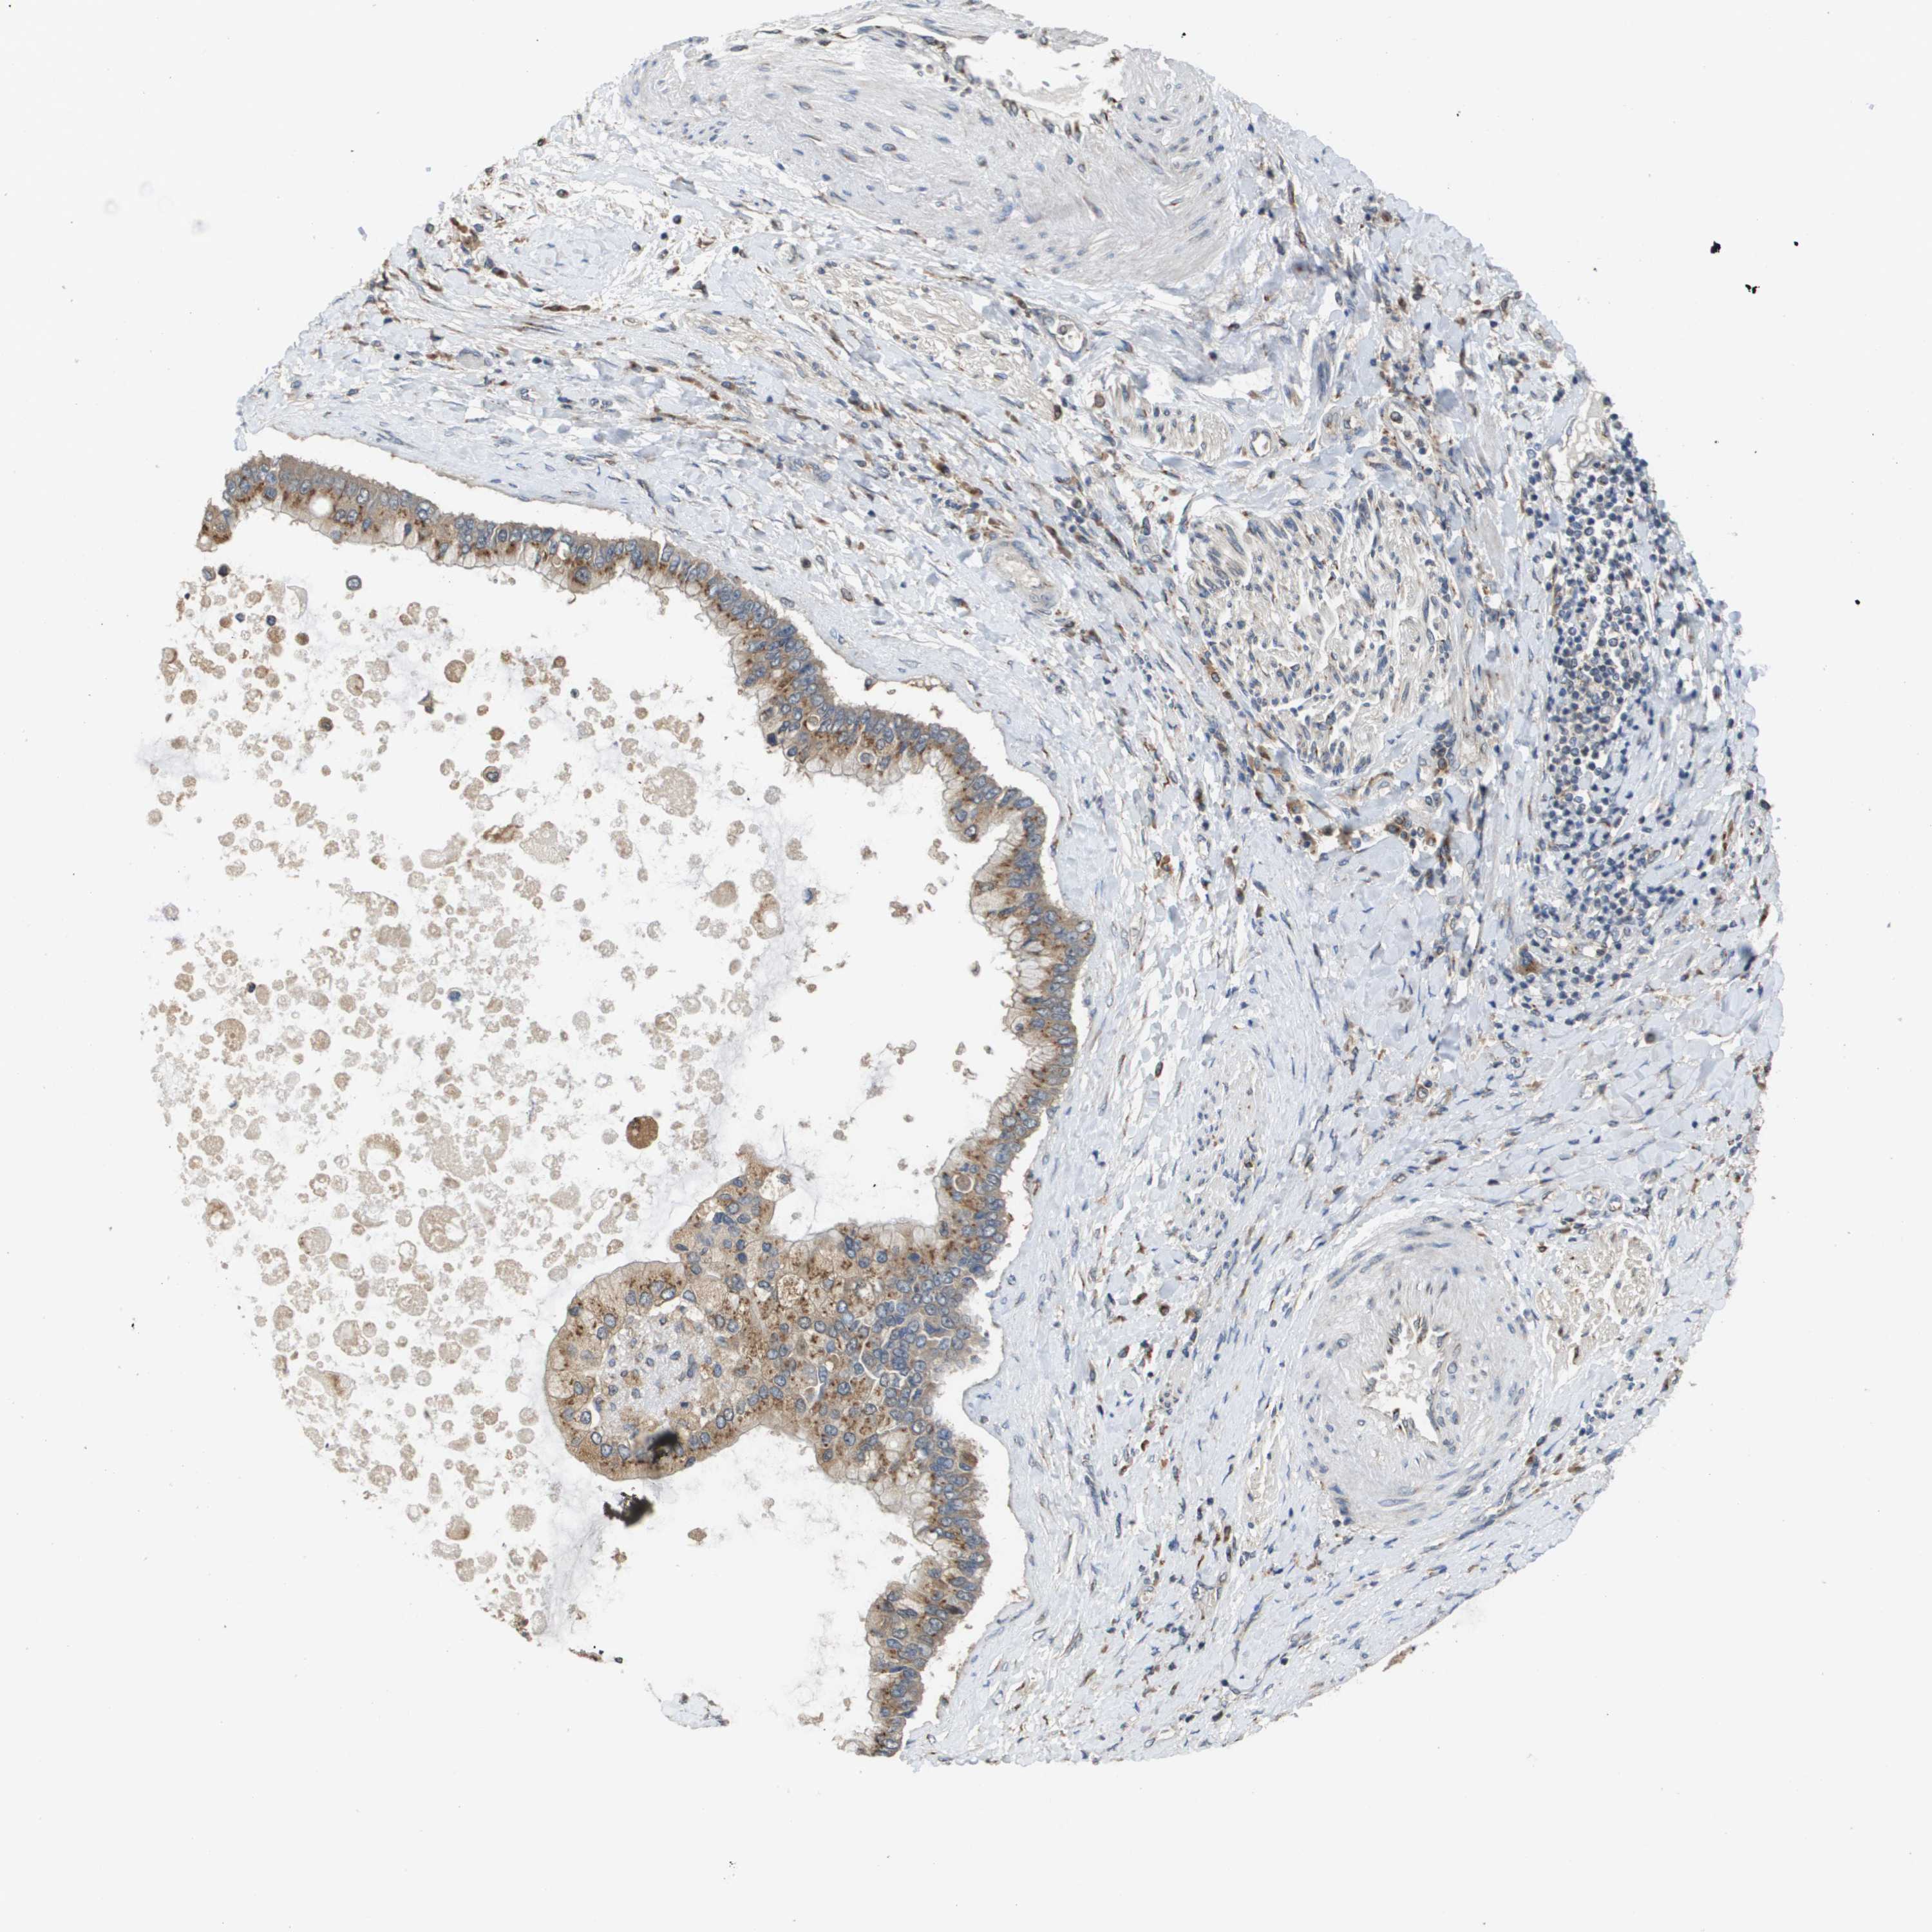

LIVER CANCER - Protein expressioni

A mouse-over function shows sample information and annotation data. Click on an image to view it in a full screen mode. Samples can be filtered based on level of antibody staining by selecting one or several of the following categories: high, medium, low and not detected. The assay and annotation is described here.

Note that samples used for immunohistochemistry by the Human Protein Atlas do not correspond to samples in the TCGA dataset.

Antibody stainingi

Antibody staining in the annotated cell types in the current human tissue is reported as not detected, low, medium, or high, based on conventional immunohistochemistry profiling in selected tissues. This score is based on the combination of the staining intensity and fraction of stained cells.

Each image is clickable and will lead to virtual microscopy that enables deeper exploration of all samples and also displays staining intensity scores, fraction scores and subcellular localization as well as patient and tissue information for each sample.

Antibody HPA006277

Antibody HPA006507

Antibody CAB017027

Staining

High

Medium

Low

Not detected

Intensity

Strong

Moderate

Weak

Negative

Quantity

>75%

75%-25%

<25%

None

Location

Nuclear

Cytoplasmic/membranous

Cytoplasmic/membranous,nuclear

Cholangiocarcinoma

Carcinoma, Hepatocellular, NOS